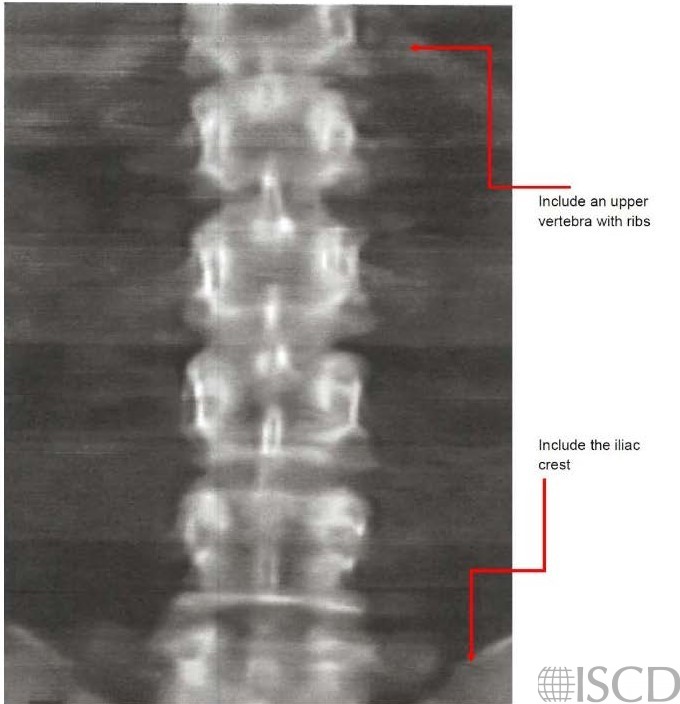

An upper vertebra with ribs and the iliac rest should be included in the scan to help with determination of vertebral leves.

The patient should be in the middle of the scanner bed. The knees are positioned up on a block so that the back is flattened out on the table. Most blocks have different dimensions, and the height of knees elevation depends upon the height of the patient. Include a part of the thoracic spine with a vertebra with ribs and the upper part of the pelvis so that the iliac crest is visible. The iliac crest designates the L4-L5 interspace. The International Society for Clinical Densitometry (ISCD) convention is to number vertebral bodies from the bottom upwards, in this way the labelling of vertebral bodies remains the same on follow-up scans. On this scan L5 has a characteristic dog bone or I shape.

The spine is straight on the table and is parallel to the sides of the image. The spine is centered in the scan field, with roughly equal amounts of soft tissue on both sides. This won’t always be possible, especially with individuals with degenerative changes in their spine.